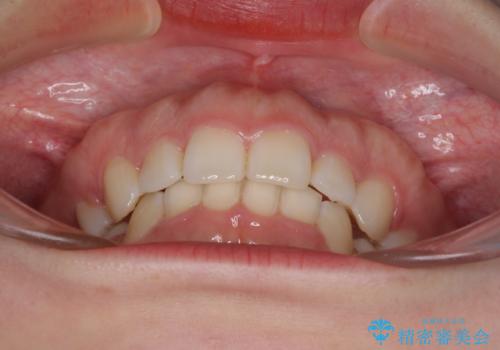

目立たない裏側矯正 抜歯矯正で口元を改善

治療期間の目安は2年半~3年間でしたが、咬み合わせにより上顎装置が頻繁に脱落してしまい、治療期間が長期化してしまいました。

期間はかかったものの、口元の張り出し感や歯のデコボコが解消され、患者様には大変満足していただけました。